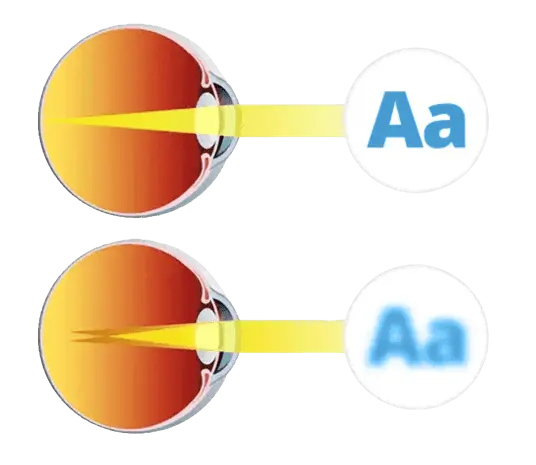

¡La causa principal de una mala visión es el mal funcionamento los músculos de los ojos!!

Los músculos oculares ayudan a enfocar correctamente la imagen en la retina.

Alteraciones musculares pueden afectar el enfoque visual natural del ojo.

Cuando el cristalino se deforma, la nitidez visual puede verse comprometida.

La elasticidad del cristalino es clave para una visión saludable y natural.

Con el tiempo, esta capacidad puede disminuir por diversos factores externos.